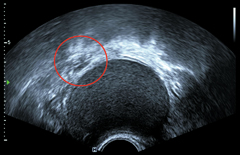

난소 종양(원 안)이 있는 환자 초음파 사진. / 삼성서울병원 제공

심한 생리통, 질 출혈, 생리양 증가 등의 증상이 반복된다면 골반초음파검사가 필요하다. 삼성서울병원 산부인과 김병기 교수는 "20~30대 여성에서 잘 나타나는 자궁근종과 난소종양 등을 잡아내는 검사"라고 말했다.